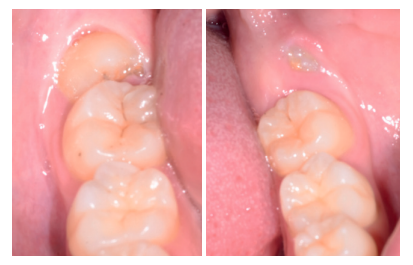

Caso clínico: se presenta un caso clínico de una mujer de 20 años, sin antecedentes médico-quirúrgicos de interés, que acudió a consulta remitida por su ortodoncista, para la extracción de un premolar maxilar retenido, en posición invertida. Tras la extracción del premolar y del tercer molar inferior retenidos, se obtuvo dentina procedente de ambos, para la regeneración ósea guiada del defecto resultante de la extracción del premolar, realizando revisiones a la semana y a los 4 meses de la intervención.

Clinical case: a clinical case of a 20-year-old woman is presented, with no interesting medical record, who went to dental clinic for removal of an inverse maxillary bicuspid retained. After maxillary bicuspid and lower third molar extractions, autogenous dentin was obtained from both teeth, to perform a guided bone regeneration of the bicuspid defect. A week and 4-month check-up were carried out.